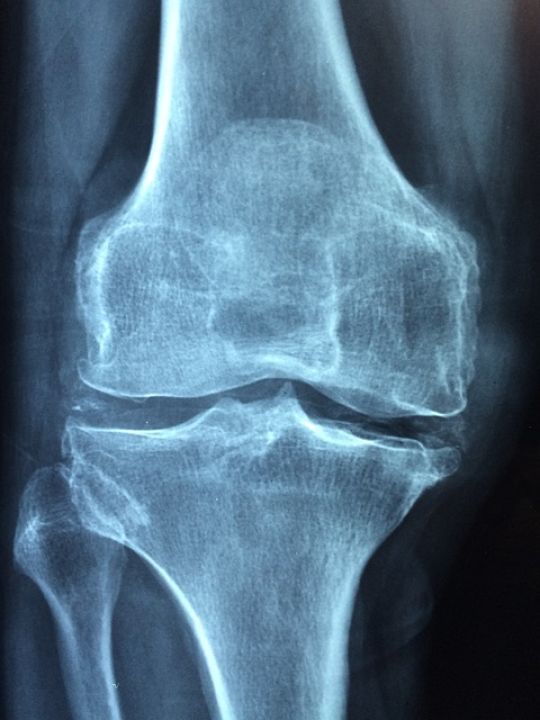

USG kolana to badanie obrazowe wykorzystujące fale dźwiękowe do uzyskania uzyskania wglądu w stawu kolanowego. Pozwala na wydajną ocenę różnych struktur anatomicznych - przede wszystkim kości, chrząstek, ścięgien, więzadeł oraz torebki stawowej. Decyzję o jego przeprowadzeniu lekarz podejmuje przede wszystkim w następujących przypadkach: